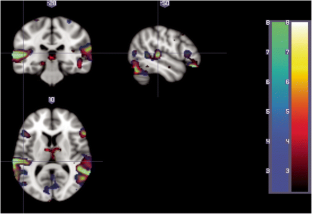

Generalized Fixation-off Sensitivity (CGE-FoS) patients present abnormal EEG patterns when losing fixation. In the present work, we studied two CGE-FoS epileptic patients with simultaneous EEG-fMRI. We aim to identify brain areas that are specifically related to the pathology by identifying the brain networks that are related to the EEG brain altered rhythms. Three main analyses were performed: EEG standalone, where the voltage fluctuations in delta, alpha, and beta EEG bands were obtained; fMRI standalone, where resting-state fMRI ICA analyses for opened and closed eyes conditions were computed per subject; and, EEG-informed fMRI, where EEG delta, alpha and beta oscillations were used to analyze fMRI. Patient 1 showed EEG abnormalities for lower beta band EEG brain rhythm. Fluctuations of this rhythm were correlated with a brain network mainly composed by temporo-frontal areas only found in the closed eyes condition. Patient 2 presented alterations in all the EEG brain rhythms (delta, alpha, beta) under study when closing eyes. Several biologically relevant brain networks highly correlated (r > 0.7) to each other in the closed eyes condition were found. EEG-informed fMRI results in patient 2 showed hypersynchronized patterns in the fMRI correlation spatial maps. The obtained findings allow a differential diagnosis for each patient and different profiles with respect to healthy volunteers. The results suggest a different disruption in the functional brain networks of these patients that depends on their altered brain rhythms. This knowledge could be used to treat these patients by novel brain stimulation approaches targeting specific altered brain networks in each patient.

Fig. 1

Fig. 2

Fig. 3

Fig. 4

Fig. 5

Fig. 6

Fig. 7

Fig. 8

Fig. 9